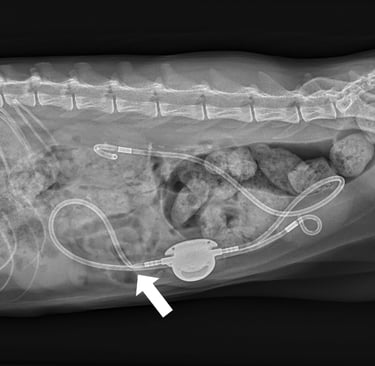

O SIDUS é um dispositivo médico veterinário indicado para desviar o fluxo da urina diretamente da bexiga para o exterior do organismo, contornando obstruções da uretra que não podem ser resolvidas por métodos convencionais.

O dispositivo cria uma nova via de eliminação da urina, conectando a bexiga a um reservatório subcutâneo, por meio de um sistema de cateteres.